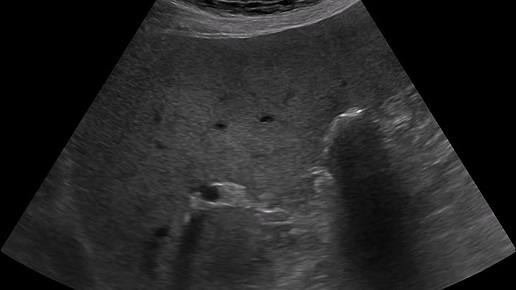

Ультразвуковые находки от врача УЗД Зорина Я.П.

Видео к статье "А ведь как похоже..." https://dzen.ru/a/aT_LeSB3aHHkpEj4